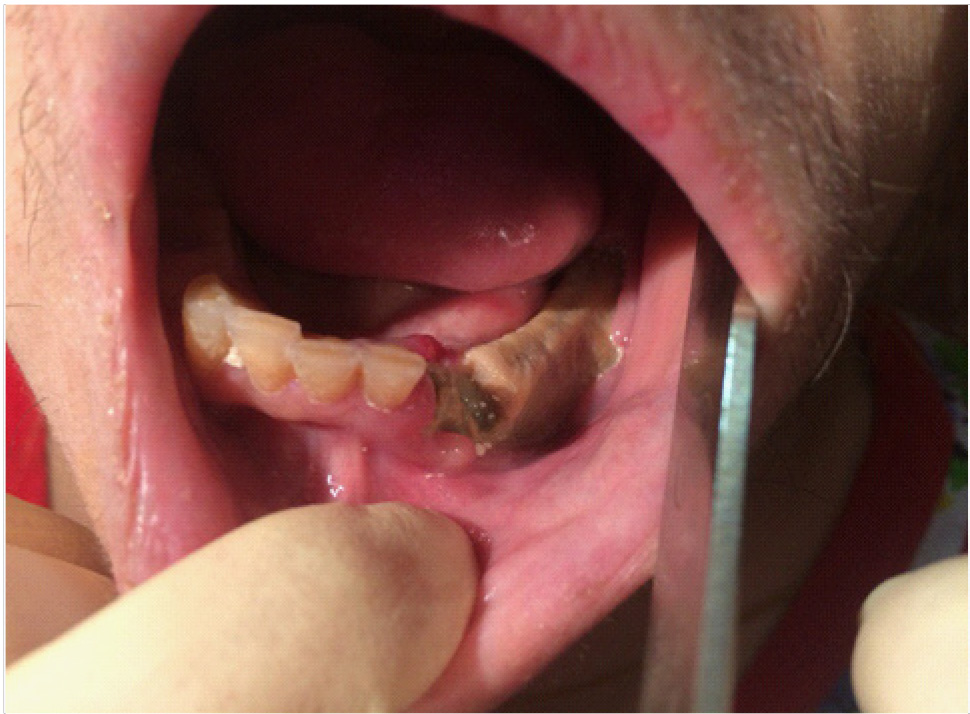

В полости рта: лунки 4.7, 4.5 зубов выполнены рыхлыми грануляциями с субтотальным остеонекрозом альвеолярной части нижней челюсти справа (рис. 2).

Рис. 2. Клинические проявления бисфосфонатного остеонекроза нижней челюсти справа у пациентки Б. в 2022 г.

В полости рта: лунки 3.2, 3.3 зубов в субтотальном остеонекрозе альвеолярной части нижней челюсти слева. На слизистой оболочке альвеолярной части нижней челюсти справа определяется язва размером до 1,0 см с инфильтрированными краями, дно язвы выполнено некротическими массами (рис. 7).

Рис. 7. Клинические проявление бисфосфонатного остеонекроза нижней челюсти слева